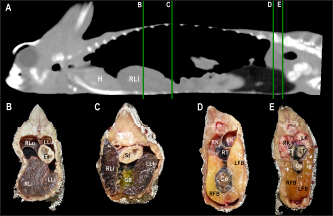

Heart, liver, including caudal vena cava (CVC), hepatic vessels, and gallbladder, esophagus, stomach, intestines, cloaca, gonads, fat bodies, kidneys, and when distended, urinary bladder were identified in the CT images with the aid of the anatomical sections (Fig. 4). The spleen, pancreas, and adrenal glands could not be identified. Measurement values of the liver, testes, fat bodies, and kidneys observed in CT in veiled and panther chameleons are seen in Table 1.

Fig. 5. Sagittal precontrast CT image displayed in soft tissue window (A) and selected corresponding transverse images represented as green line section, displayed in soft tissue (B, D–G) and lung window (C) at the level of the lungs, liver (D), gastrointestinal tract (E), fat bodies (F), and kidneys/urinary bladder (G) in a panther chameleon (F. pardalis). The right of the patient is on the left of the image. RLu, right lung; LLu, left lung; Es, esophagus; RLi, right liver lobe; LLi, left liver lobe; St, stomach; I, intestine; GB, gallbladder; RK, right kidney; LK, left kidney; RT, right testicle; LT, left testicle; Co, colon; RFB, right fat body; LFB, left fat body; U, urinary bladder with intraluminal content (urate salts) in the lumen visualized as multiple irregular mineral attenuating structures.

Fig. 6. Sagittal right paramedian precontrast CT image displayed in soft tissue window (A) and selected corresponding transverse images represented as green line section, displayed in soft tissue window at the level of the gallbladder (B), fat bodies (C), and kidneys/urinary bladder (D) in a veiled chameleon (C. calyptratus). H, heart; RLu, right lung; LLu, left lung; Es, esophagus; RLi, right liver lobe; LLi, left liver lobe; GB, gallbladder; RK, right kidney; LK, left kidney; RT, right testicle; LT, left testicle; I, intestine; RFB, right fat body; LFB, left fat body; U, urinary bladder; LF, left femur; RF, right femur; PB, pelvic bone.